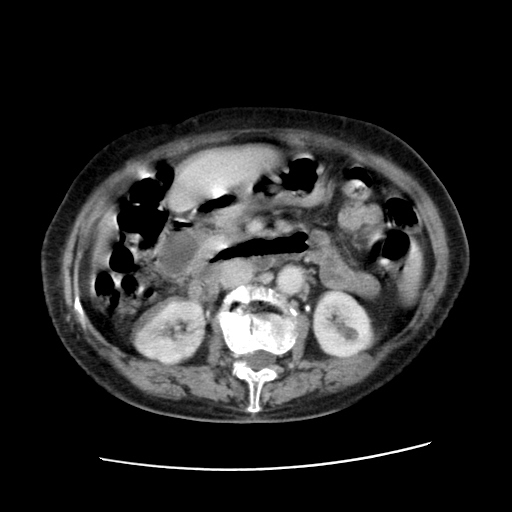

标题: CT25203:上腹部增强,看看

女,77.无不适

肝内胆管扩张,胆囊炎,胆囊窝积液。 右侧胸腔少量积液。

肝旁多发胆囊状液体影考虑肠腔积液基中部分囊状景不多外胆囊

肠子那块乱乱的没整明白

肝右叶肝内胆管结石并肝内胆管扩张。胆总管下段梗阻,考虑壶腹部占位。